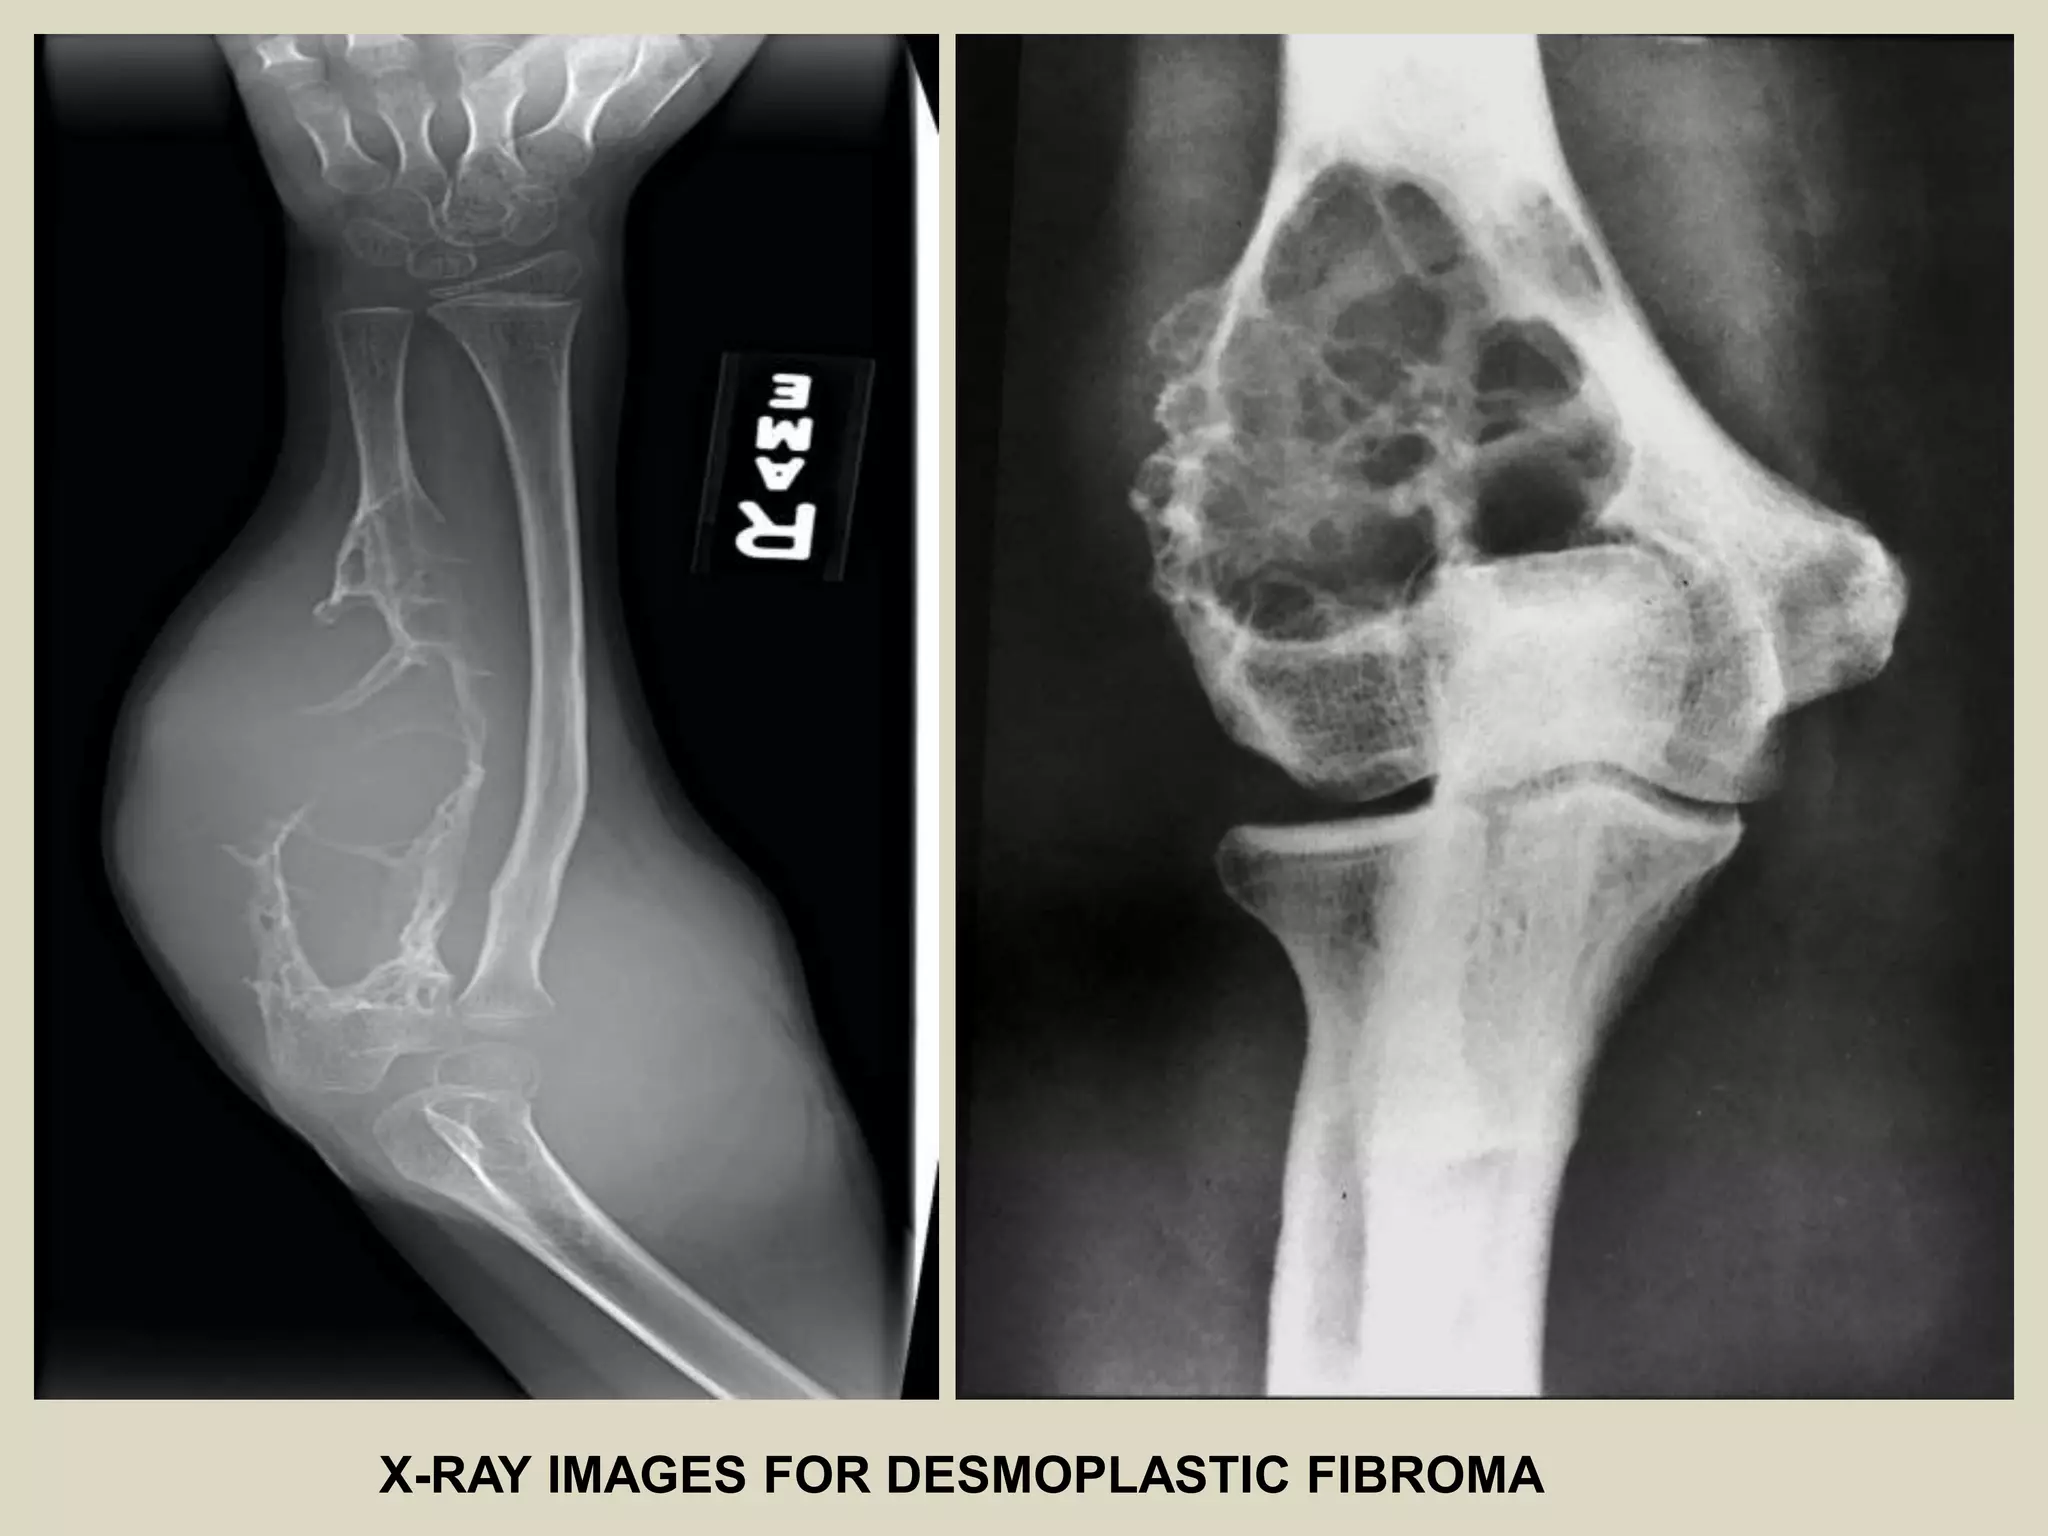

DESMOPLASTIC FIBROMA

Definition:

- Rare, locally aggressive, solitary tumor microscopically composed of well

differentiated myofibroblasts with abundand collagen production.

Epidemiology:

- Rare, 0.1% of all primary bone tumors.

- It tends to occur in adolescent and young adults with near equal gender distribution.

Sites of involvement:

- May involve any bone but is most frequent in mandible.

Clinical findings:

- Pain and swelling of the affected area are the most common symptoms.

- Pathologic fracture or deformity of the affected bone can occasionally be presenting

symptom.

Imaging:

- Usually well defined, radiolucent lesion that may expand host lesion.

- Inter lesional trabeculation is frequent.

- Larger lesion often show destruction of overlying cortex with extension into soft

tissue.

- Features of more aggressive growth pattern with irregular, ill-defined margins and

pathological fracture may be present.

- Honeycombed or moth-eaten patterns have been described.

- Erosive, destructive pattern may mimic other, more aggressive lesions.

- DF has low signal intensity in both T1 and T2 weighted MRI images.

X-RAY IMAGES FOR DESMOPLASTIC FIBROMA